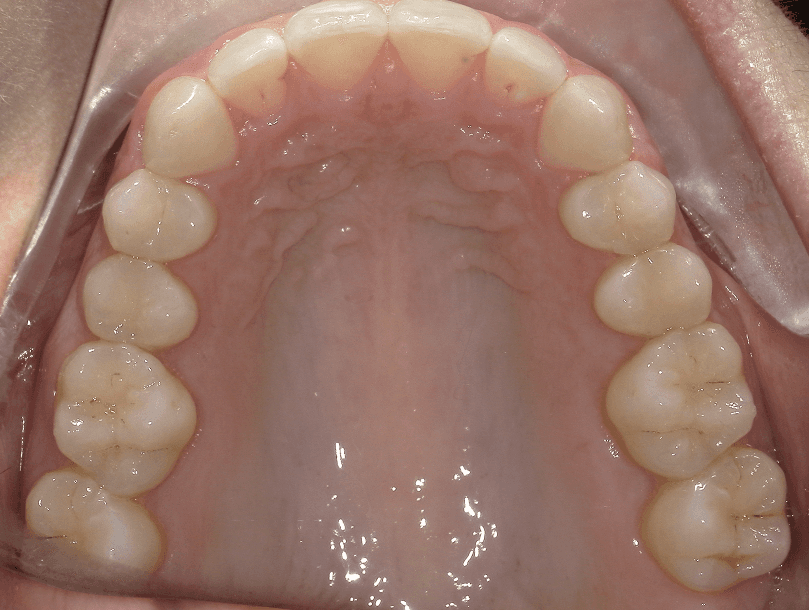

Final results

INTRAORAL